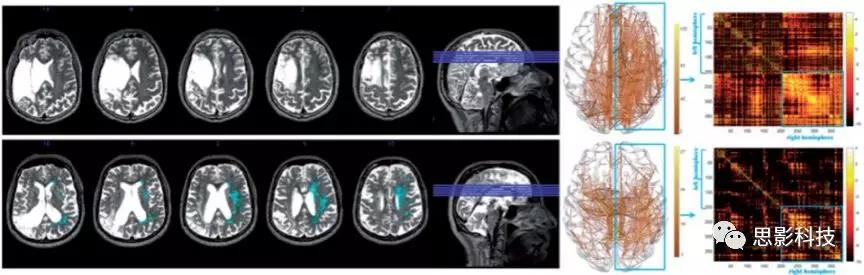

采用由Fazekas等人于1987年完善的(the Fazekas scale)評分量表,評估側(cè)大腦半球(病灶對側(cè)半球)白質(zhì)高信號的表現(xiàn)與程度,因為該研究分析的是腦小血管病的影響,而非大血管損傷導(dǎo)致白質(zhì)損傷造成的失語。通過T2 MRI,對側(cè)腦室旁WMHPVH)、深部腦白質(zhì)WMHdeep WMH)分別進行評估,共4個等級0-30WMH,3融合性WMH)?;诖耍?span>PVH(側(cè)腦室旁白質(zhì)高信號)與deep WMH(深部白質(zhì)高信號)評分均為0作為對照組,為卒中損傷而無腦白質(zhì)高信號組。相對于評分>0的被試為存在卒中及WMH。2為兩名被試的PVHdeep WMH評分舉例。

2.該研究2例被試T2 MRI圖。左側(cè)PVH、deep WMH由藍色標記,以及相應(yīng)的白質(zhì)追蹤及結(jié)構(gòu)連接矩陣(x軸、y軸與AICHA感興趣區(qū)域一致,顏色越亮區(qū)域見連接度越高)。第一列被試卒中后無WMH,第二列被試WMH最嚴重(PVH(側(cè)腦室旁白質(zhì)高信號)3分,deep WMH(深部白質(zhì)高信號)3分)。連接矩陣圖顯示:WMH評分越嚴重,連接越稀疏(被試2相較于被試1),尤其是長程投射的大腦區(qū)域,如額葉。